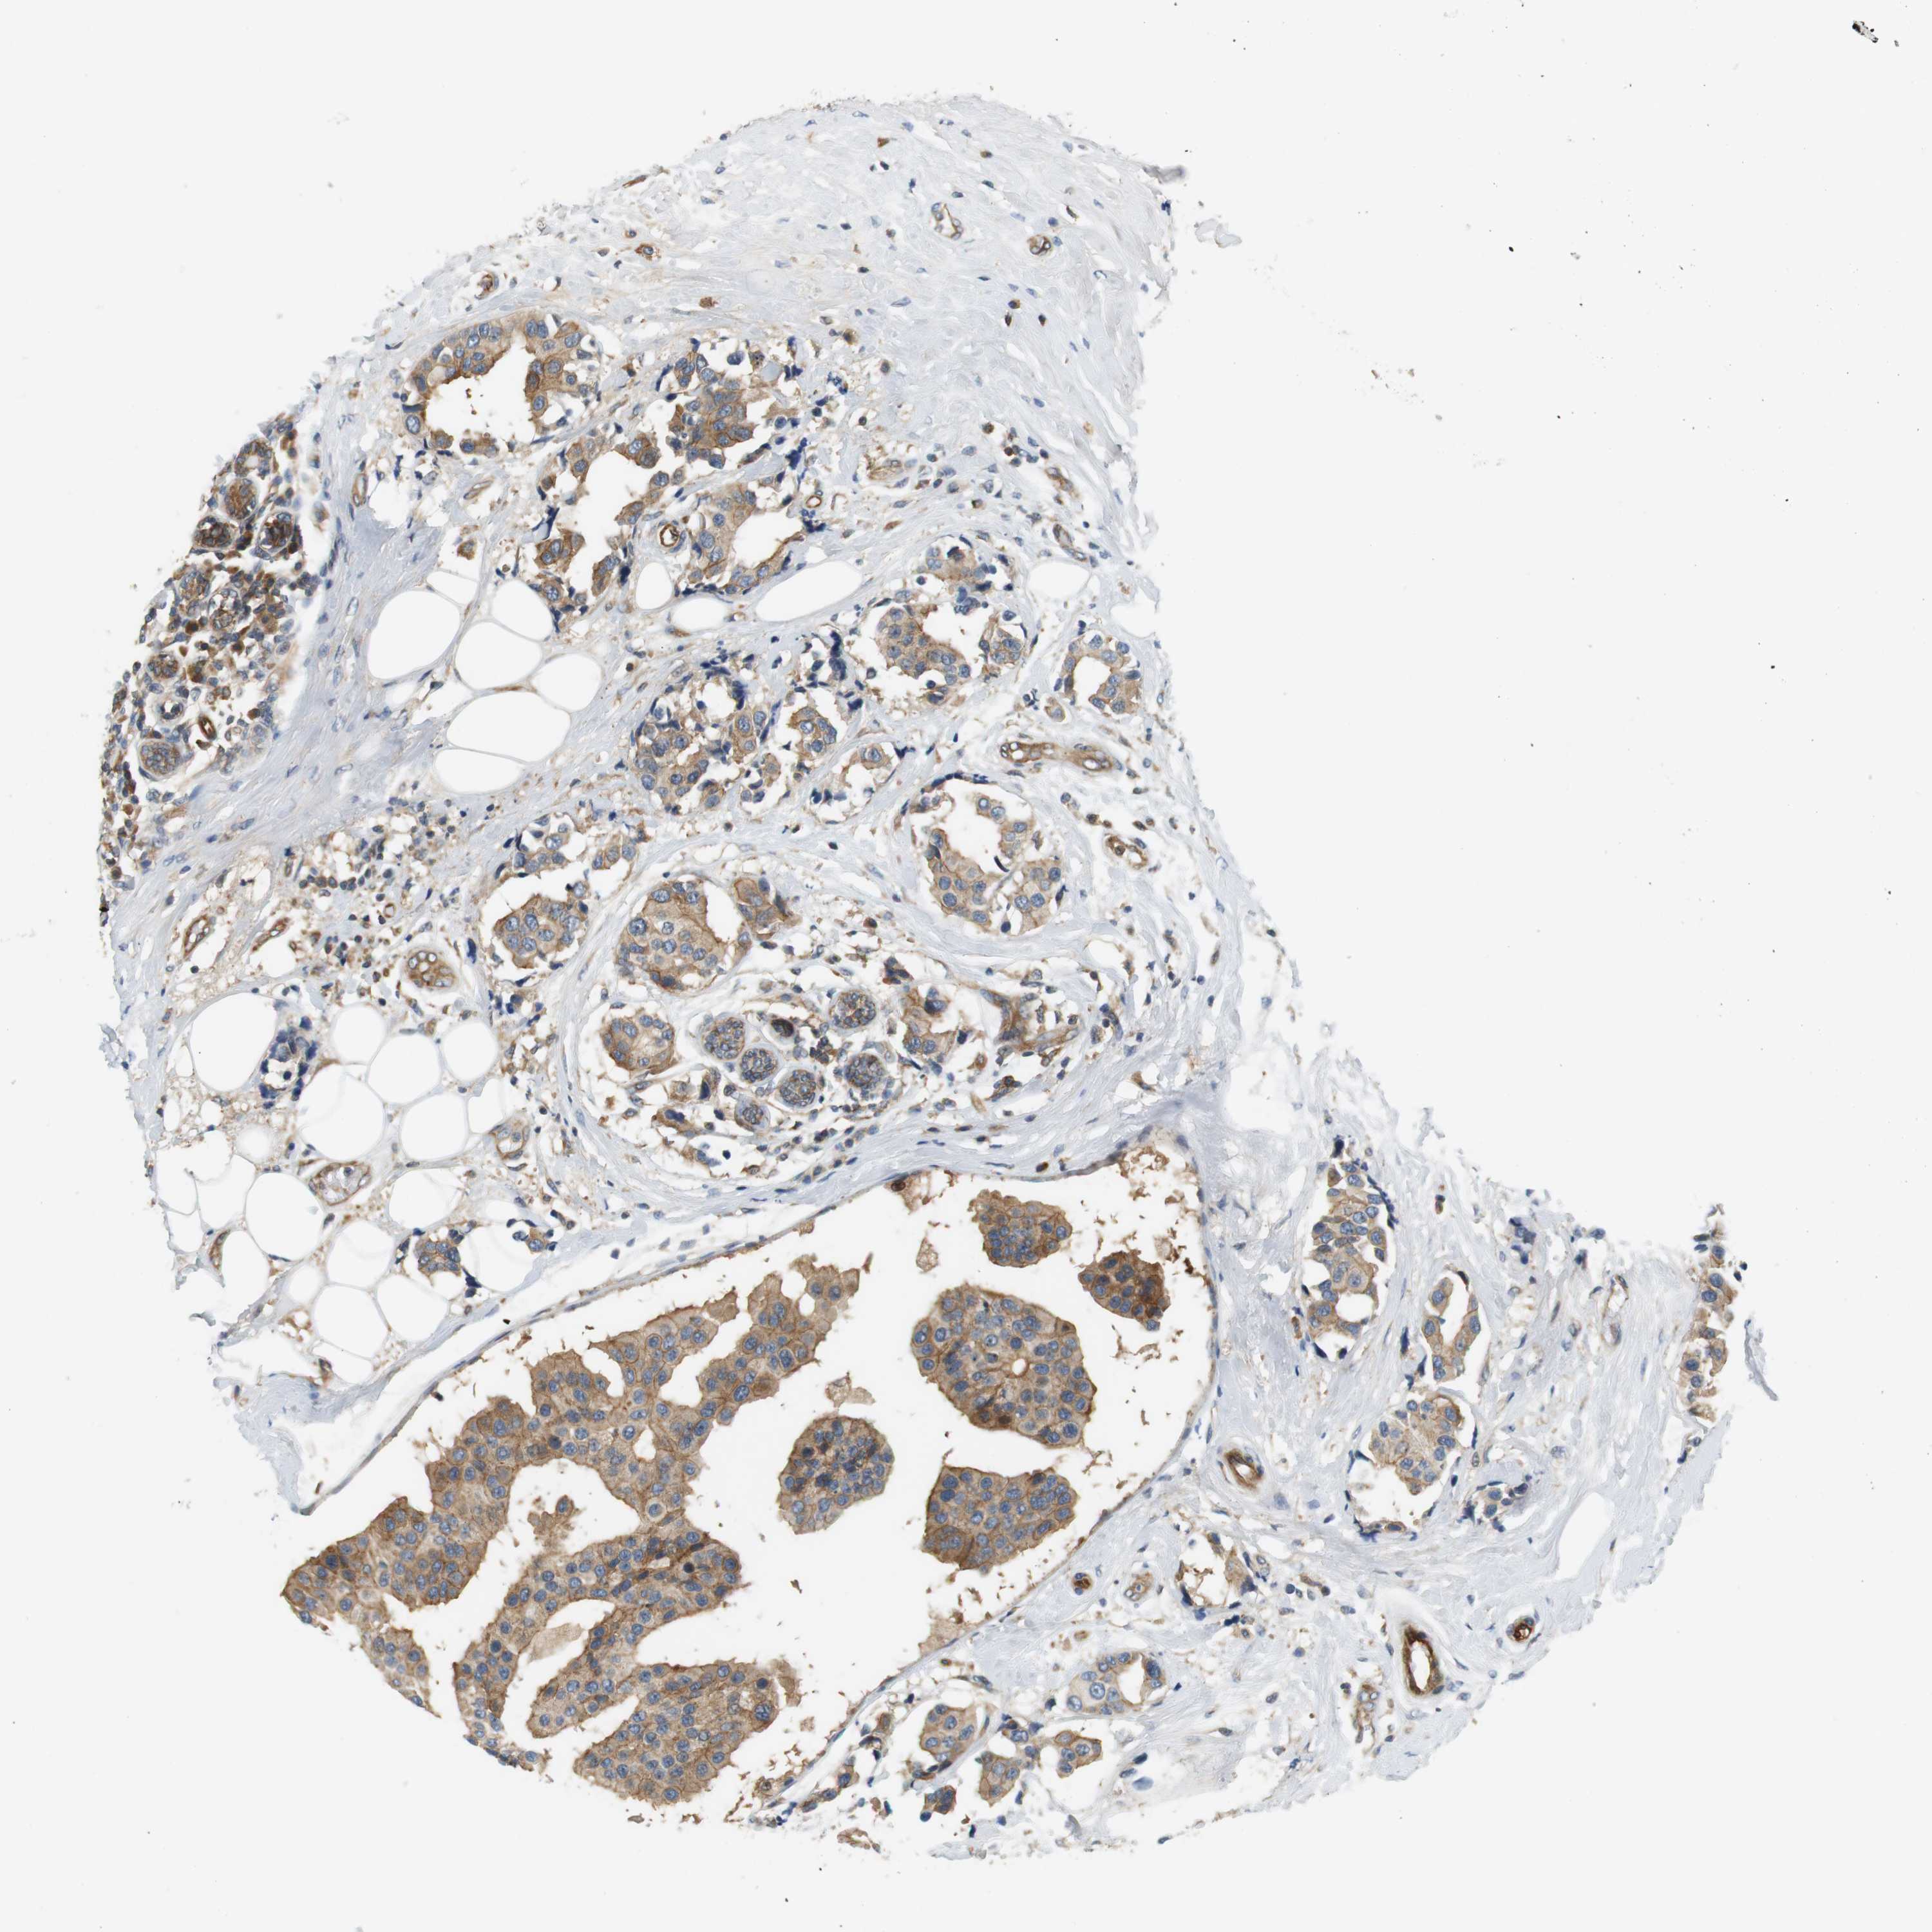

CANCER BREAST CANCER Show tissue menu

BRCA TCGA BRCA VALIDATION PROTEIN EXPRESSION

ANTIBODIES

AND

VALIDATION